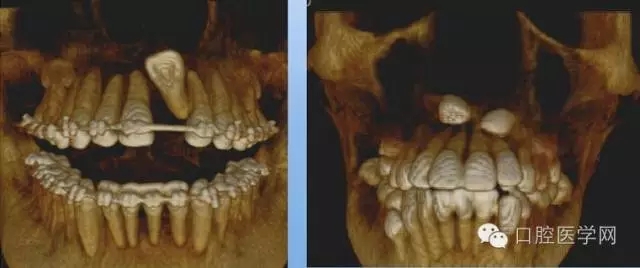

3.牙齒數(shù)目異常

額外牙

X線表現(xiàn):最多見于上頜兩中切牙之間;圓錐形,根短小;拍攝X線片可確定額外牙的數(shù)目、位置、形態(tài)與鄰牙的關(guān)系。